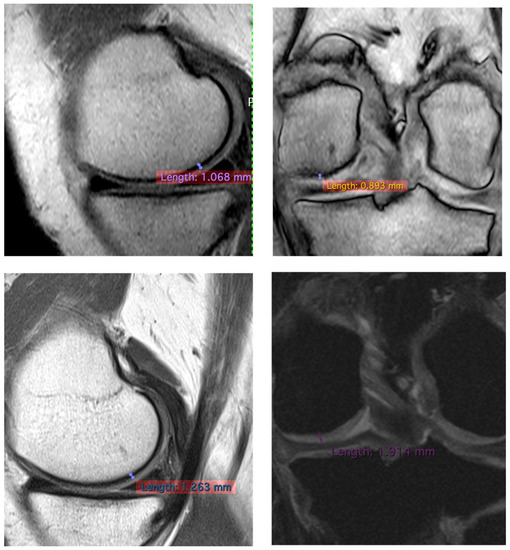

| Patients | Pre/Femoral Lateral Condyles | 3 Years/Femoral Lateral Condyles | Difference |

|---|---|---|---|

| 1 | 1.064 mm | 1.226 mm | +15.22% |

| 2 | 1.339 mm | 1.472 mm | +9.32% |

| 3 | 1.068 mm | 1.263 mm | −14.20% |

| 1 | 1.223 mm | 1.555 mm | +27.14% |

| 2 | 1.489 mm | 1.882 mm | +26.39% |

| 3 | 0.893 mm | 1.914 mm | +114.33% |